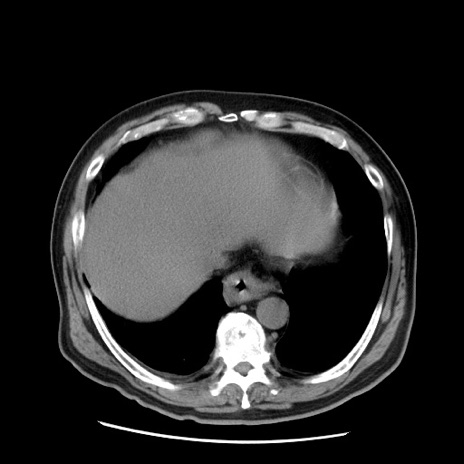

症例20(横断像)

【症例】 60歳代男性

【主訴】 腹部膨満、嘔吐

【現病歴】5日前頃より倦怠感を認め食事量減少し4日前の朝嘔吐、食事摂取困難となった。 3日前近医受診し点滴施行され整腸剤などを処方された。 当日他院を受診し、腹部膨満著明、炎症反応の上昇(CRP10.8、WBC11200)あり、紹介受診となる。

【身体所見】 意識JCS1 受け答えがはっきりしないBP 111/57mHg、 P 67bpm、、BT35.2°C、SpO2 97%(RA)、 腹部:膨隆、打診で鼓音あり、全体的に圧痛有り、腸蠕動音(-)、反跳痛ははっきりせず。

【データ】WBC 11400、CRP 14.20